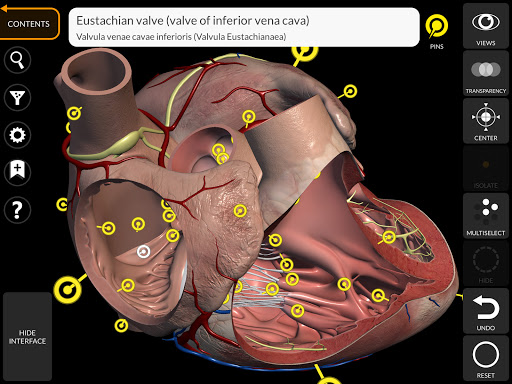

"Anatomy 3D Atlas" дозволяє легко та інтерактивно вивчати анатомію людини.

Завдяки простому та інтуїтивно зрозумілому інтерфейсу можна спостерігати кожну анатомічну структуру під будь-яким кутом.

Анатомічні 3D-моделі особливо деталізовані та мають текстури з роздільною здатністю до 4k.

• Серцево-судинна система

• Вибравши модель або шпильку, з’явиться відповідний анатомічний термін

• Анатомічні терміни можуть відображатися двома мовами одночасно.